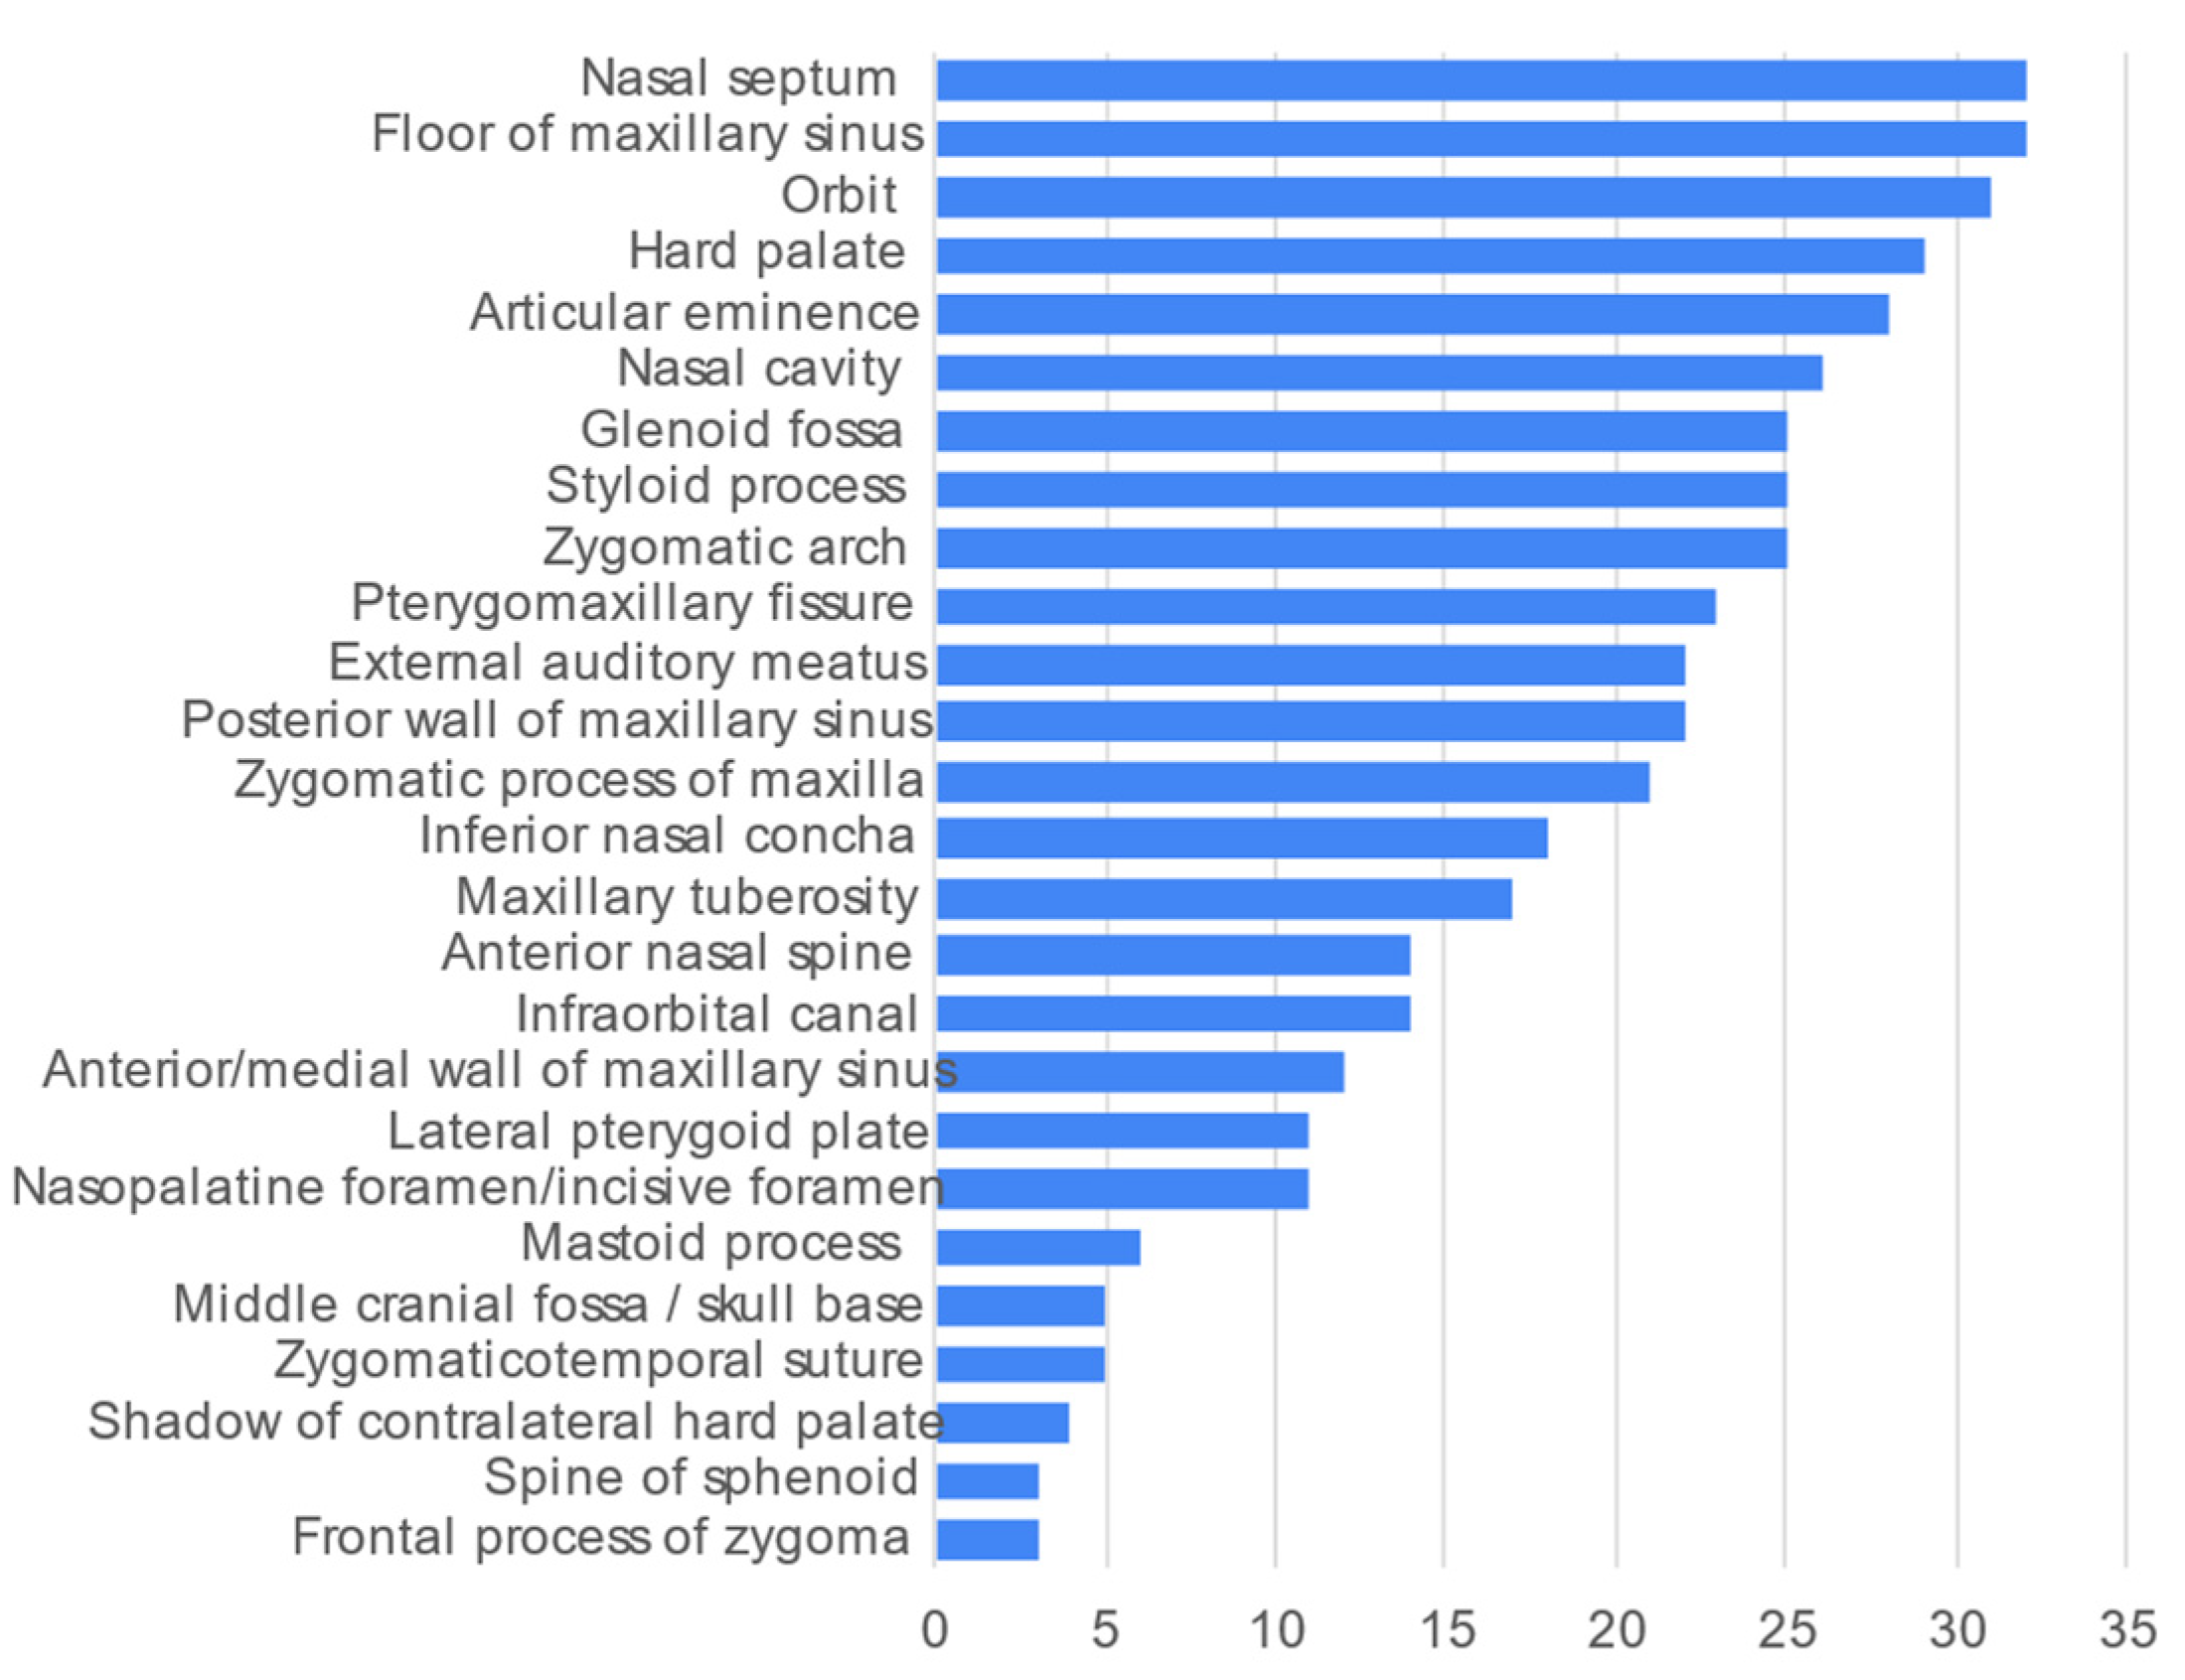

3. Results